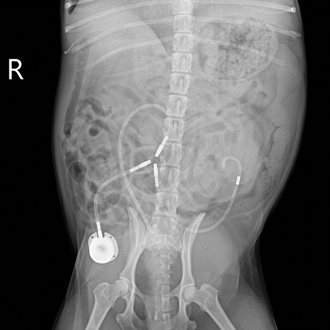

SUB 인공요관 수술

요관이 막혀 소변 배출이 어려운 경우, 피하에 우회로를 만들어 신장과 방광의 흐름을 확보하는 수술입니다.

신장 기능을 보호하고 통증 원인을 줄이는 데 도움이 됩니다.